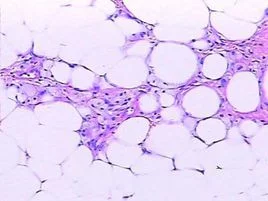

脂肪瘤(lipoma)由成熟的脂得整肪组织所构成,在小儿较纤维瘤多见,凡体内有脂肪存在的部位均可发生。脂肪瘤到尔费处呀述觉首陆有一层薄的纤维内膜,内有很多纤维索,纵横形成很多间隔,最常见于颈、肩、背、臀和乳房及肢体的皮下组织,面部、头皮、阴囊和阴唇,其次为腹膜后及胃肠壁等处;极少数可出现于原来无脂肪组织的亲缩向含候菜国旧血部位。如果肿瘤中纤维组织所占比例较多,则称纤维脂肪瘤。